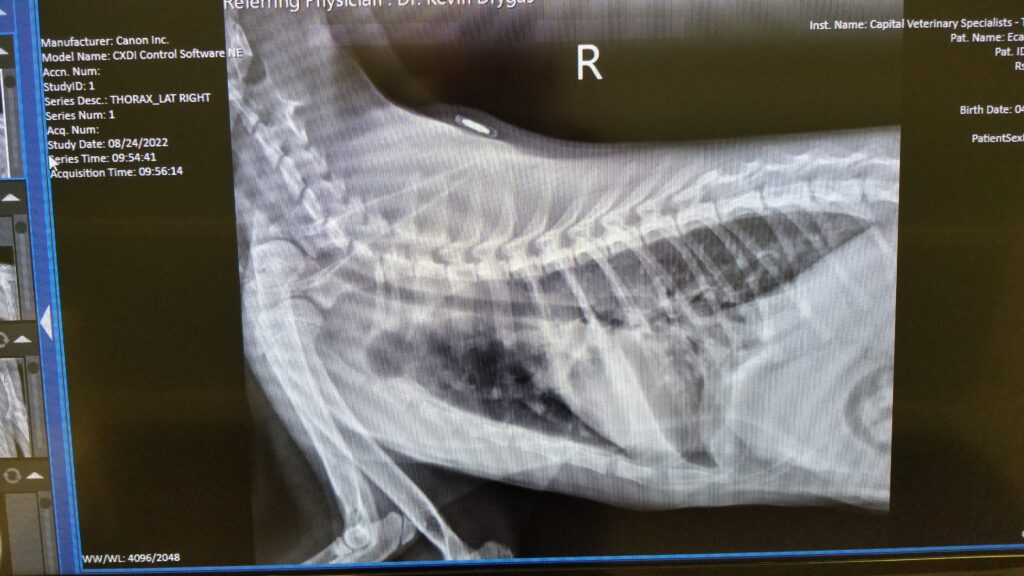

Bella went on yet another trip to the vet, she was not happy about the turn of events.

and x-ray of her insides, they’re not where they’re supposed to be and her ribs are all wonky. Also, you can see her chip in this x-ray, which is kinda cool.